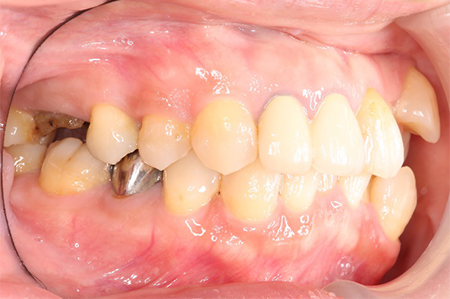

この患者様は長い事歯科医院には通っておらず、下の歯は前歯以外は全て崩壊していることが分かります。

様々なことを鑑み、患者様とも何度も話し合いを行い、下の奥歯には必要最低限のインプラントを、他の歯も外科処置を施しなるべく歯を抜かない方法を取りました。

最終的に抜歯した本数は下の歯5本。上の歯に関しては全て残すことが出来ました。

奥歯があることで前歯の負担を減らし、前歯を失うリスクを下げることが出来ます。

| 治療期間 | 2年 |

| 費用 | 歯周外科治療 3万円×17本 GBR 15万円×2部位 インプラント 37万円×4本 補綴 ジルコニアクラウン 15万円×24本 |